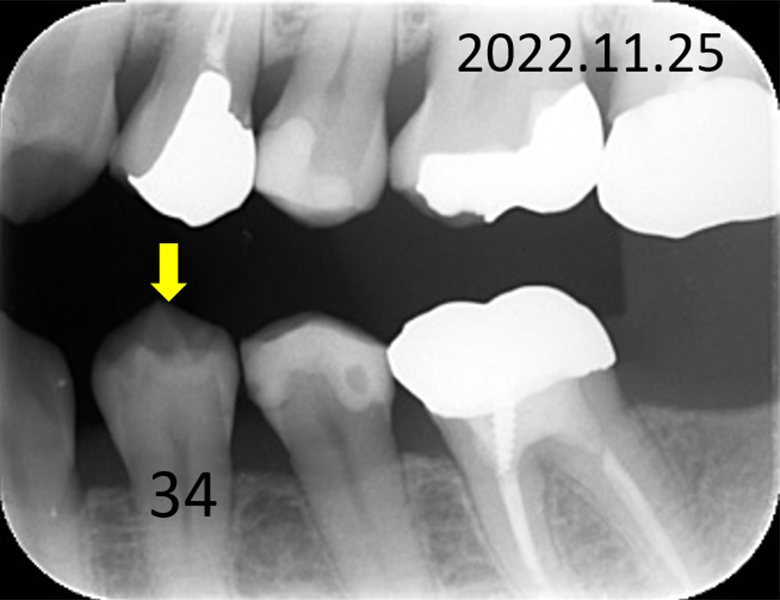

症例③ 下顎小臼歯 小窩や裂溝の虫歯 54歳女性

初診時口腔内写真 |

![]() 初診時レントゲン写真 |

約3年後の口腔内写真 |

![]() 約3年後のレントゲン写真 |

症例③

主訴 |

正しい口腔ケアを知り、健康的になりたい。 |

診断 |

下小臼歯の初期虫歯 |

治療 |

経過観察 |

期間 |

経過観察中 |

費用 |

0円 |

治療リスク |

虫歯進行の可能性 |